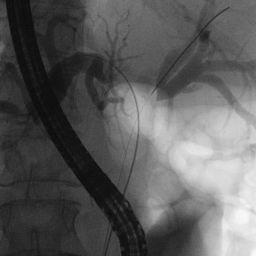

- Endoscopic Retrograde Cholangiopancreatography (ERCP): A procedure that uses a camera to examine the bile ducts and take tissue samples for testing.